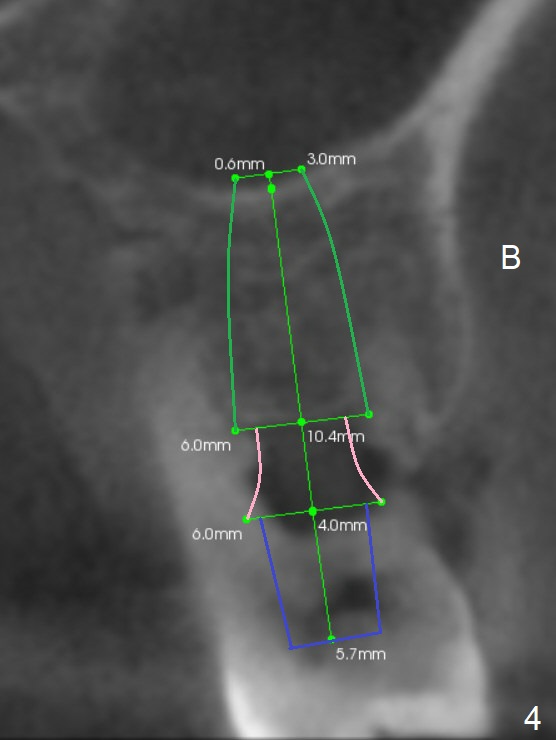

A 44-year-old man is a typical patient with chronic periodontitis (Fig.1). Periimplantitis develops following immediate implant at #31 (Fig.2). The symptom (bleeding) improves after bone graft and use of Water Pik. Now the tooth #14 appears to be non-salvageable because of gingival hemorrhage and deep pockets after previous osseous surgery. To prevent periimplantitis, an immediate implant does not need to be large or long. It has to be placed deep, and in the middle of the native bone, surrounded by bone graft. To facilitate wound healing, draw 3 tubes of blood for PRF. One of them is processed for plug in case of sinus lift. To prevent the buccal gingiva collapse, the buccal portion of the immediate provisional should extend into the socket. If the gingiva is around 4 mm, use IBS implant (Fig.3,4). Otherwise, a SM implant will be used after extraction (Clindamycin), since abutments have cuffs as long as 4.5 and 6 mm so that it is easy to place an implant as deep as possible. Initial depth will be 9 mm (bone-level), followed by Magic Drill (5.3 mm, if possible) and Magic expanders (4.3x10 and 4.8x11 mm, bone density 26-300 units).